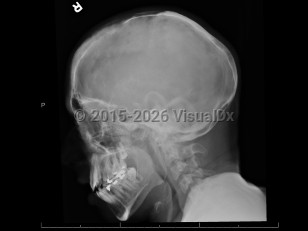

Clinical signs and symptoms vary widely and may present any time before birth or into adulthood. HPP in infancy is typically more severe and life-threatening. Neonate HPP symptoms include weakening and softening of bones, skeletal abnormalities, poor feeding, failure to thrive, respiratory problems, and hypercalcemia, which may cause vomiting or renal complications. The childhood / adulthood presentation is usually less severe. One of the first presenting signs in children is early loss of baby teeth. Children may also have short stature with bowed legs or knock knees, enlarged wrist and ankle joints, and an abnormally shaped skull. Adults presenting with HPP may have osteomalacia, recurrent foot and thigh bone fractures, and resulting chronic pain. Adult patients may also have premature loss of adult teeth, and joint pain and inflammation. The mildest form of HPP is odontohypophosphatasia, a condition affecting only the teeth and having no impact on the skeletal system; it does not affect life expectancy.